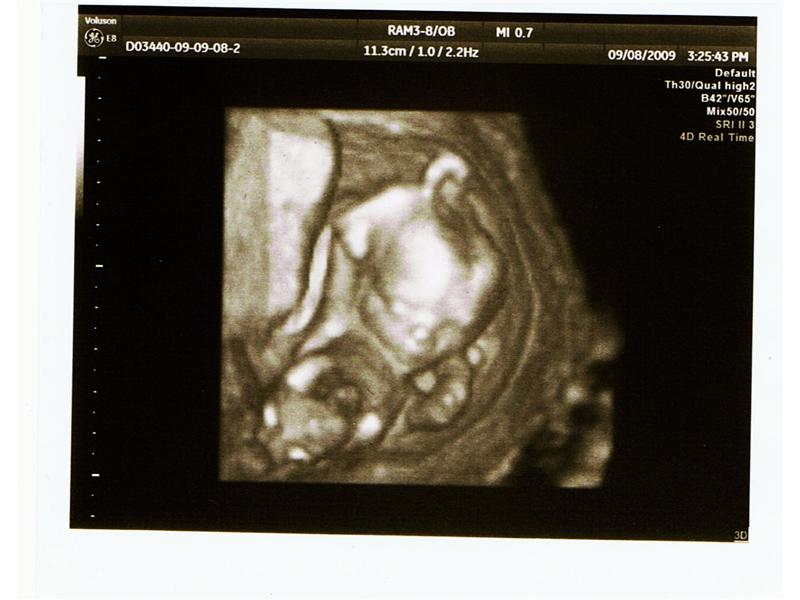

3D